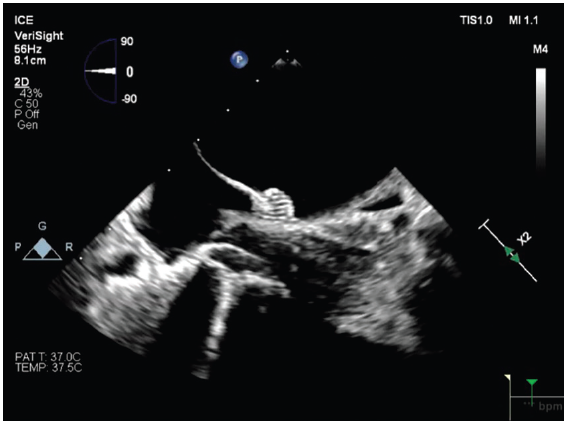

The Expanding Role of Intracardiac Echocardiography in EP: Interview With Jason Chinitz, MD Dr Chinitz discusses the central role of ICE in advancing procedural safety, efficiency, and operator control. https://t.co/miQHRKY7hZ @PhilipsHealth